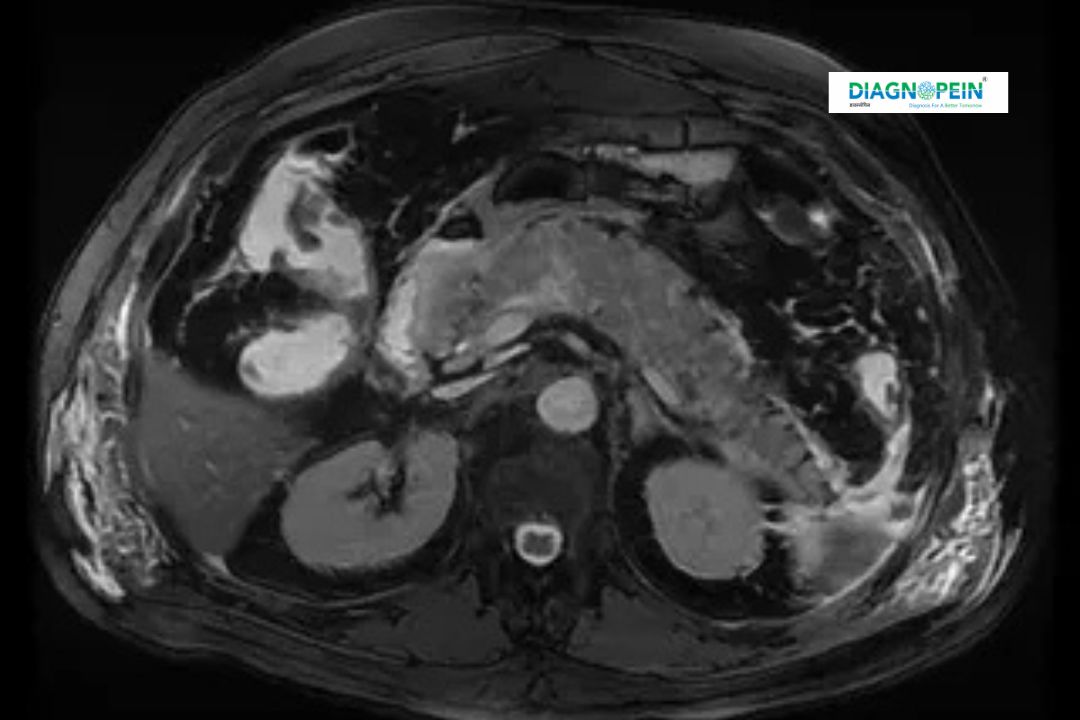

The MRI - MRCP (Magnetic Resonance Cholangiopancreatography) is an advanced non-invasive imaging technique that provides detailed images of the liver, gallbladder, bile ducts, pancreas, and pancreatic duct. Using strong magnetic fields and radio waves, this scan captures clear visuals without the use of ionizing radiation such as X-rays. At Diagnopein Diagnostic Center in Nanded, the MRI - MRCP is conducted by experienced radiologists using high-resolution MRI scanners for accurate evaluation of abdominal and pancreatic conditions.

The MRCP test focuses on imaging parameters that provide detailed visualization of:

1. Bile ducts and pancreatic ducts.

2. Gallbladder pathology including stones or inflammation.

3. Liver and pancreatic tissue contrast.

4. Fluid accumulation in or around the ducts.

5. Ductal narrowing or dilation patterns.

These comprehensive parameters help physicians accurately evaluate blockages, infections, congenital anomalies, and tumors in the hepatobiliary system.